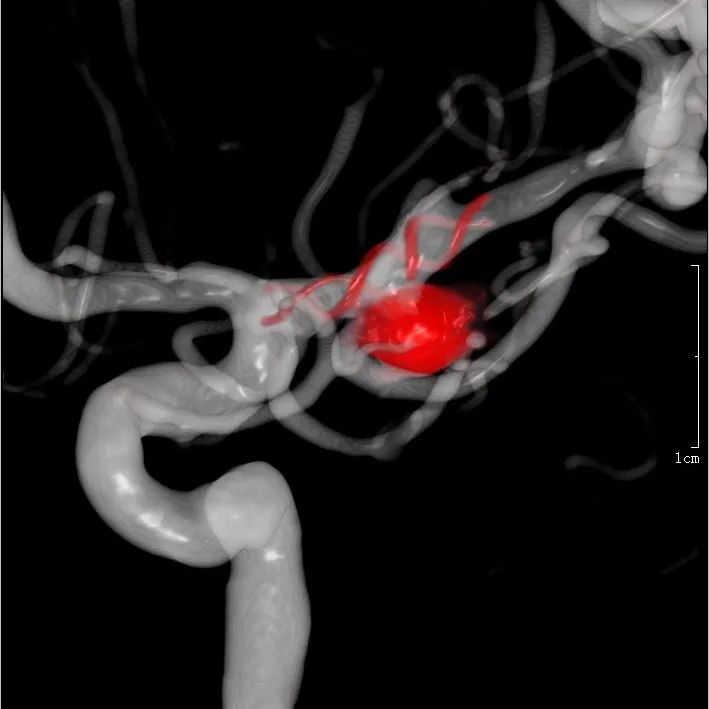

头颅CTA提示左侧优势供血前交通动脉动脉瘤。

牛角弓、颈动脉极度迂曲。

瘤颈与载瘤血管关系不甚清楚,故行压颈3D造影。